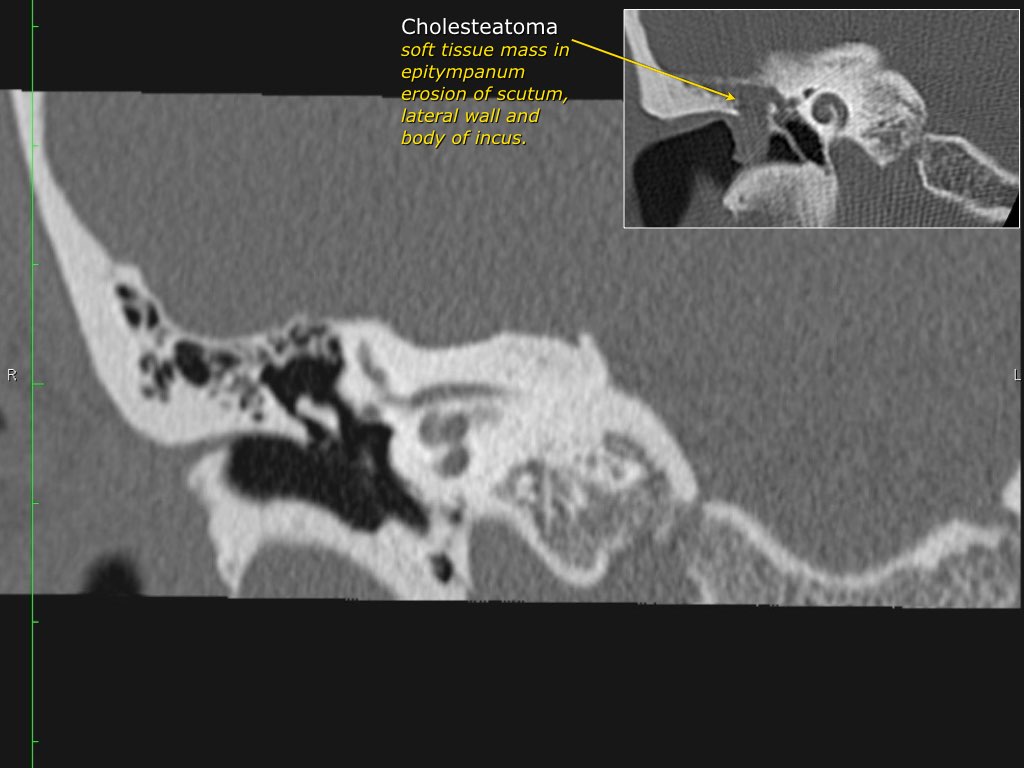

Hình ảnh một bệnh nhân có cholesteatoma.

Có một khối mô mềm ở vùng thượng nhĩ.

Lưu ý hình ảnh thủng màng nhĩ (mũi tên vàng) và bào mòn ống bán khuyên ngoài (mũi tên đỏ).

Scutum bị tù mòn.

Đây thường là cấu trúc xương đầu tiên bị bào mòn do cholesteatoma, hình thành bởi sự co kéo vào trong của pars flaccida màng nhĩ vào vùng thượng nhĩ.

Nếu quá trình co kéo tiếp tục tiến triển sẽ dẫn đến phá hủy chuỗi xương con.

Nếu cholesteatoma lan ra phía sau qua aditus ad antrum vào trong xương chũm, có thể gây bào mòn tegmen mastoideum làm lộ màng cứng, đồng thời bào mòn ống bán khuyên ngoài dẫn đến điếc và chóng mặt.